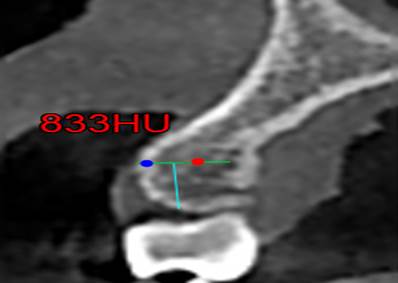

Los datos recopilados fueron número de registro, edad del paciente, sexo, corte de la zona maxilar interradicular de donde se tomó la muestra. Se llego a un consenso con los expertos donde se tomó en cuenta los siguientes puntos anatómicos para la toma de la medida mediante Unidades Homsfield.

§ Con una profundidad de 0.6 mm a través de la cortical hacia la tabla ósea que es el valor mínimo de un microtornillo ortodóntico en sentido horizontal (imagen 2) interradicular. Las Zonas a medir fueron:

Finalmente se mide las Unidades Hounsfield (UH) a 6 mm intraóseo e interradicular. (Imagen 1,2,3,4).